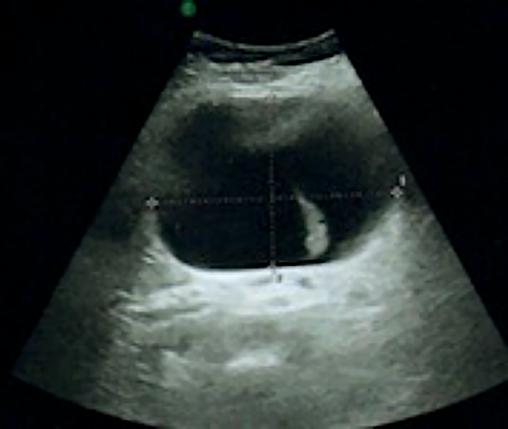

L’exploration biologique est strictement normale, sans cytolyse hépatique. L’échographie abdominale révèle un macrokyste de 10 cm à l’épigastre, contenant une cloison (fig. 1 ).

L’exploration biologique est strictement normale, sans cytolyse hépatique. L’échographie abdominale révèle un macrokyste de 10 cm à l’épigastre, contenant une cloison (